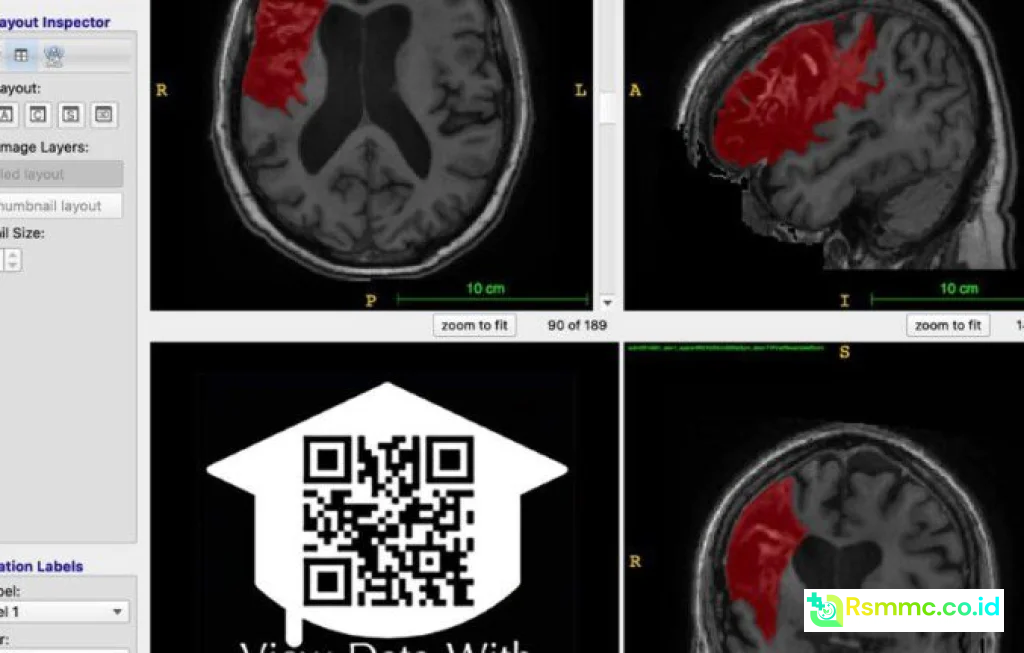

Lokasi lesi di otak

Dalam rehabilitasi stroke, tidak ada dua pasien yang benar benar sama. Lokasi lesi, usia, kondisi medis penyerta, dan dukungan sosial membuat respons terhadap terapi sangat bervariasi. Open data stroke recovery memungkinkan tenaga kesehatan melihat pola pemulihan pada ribuan bahkan jutaan pasien dengan karakteristik yang mirip.

Contohnya, seorang pasien berusia 60 tahun dengan stroke iskemik di daerah kapsula interna, kelemahan sisi kanan berat, dan riwayat diabetes. Dengan basis data terbuka, dokter dan tim rehabilitasi dapat membandingkan pasien ini dengan ribuan pasien lain yang mirip, lalu mengidentifikasi kombinasi terapi apa yang paling banyak menghasilkan pemulihan fungsi berjalan dalam 3 sampai 6 bulan.